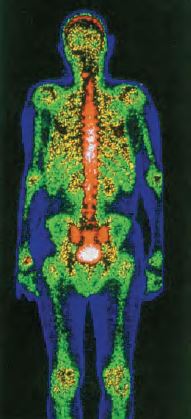

Ορισμένα ραδιοϊσότοπα έχουν αποδειχθεί πολύ αποτελεσματικά ως ιχνηθέτες σε ορισμένες διαγνωστικές διαδικασίες. Αυτό συμβαίνει γιατί τα ραδιοϊσότοπα εύκολα μπορούν να αντικαταστήσουν τα αντίστοιχα φυσικά ισότοπα, ενώ εύκολα μπορούν να ανιχνευθούν, ακόμη κι όταν βρίσκονται σε ίχνη, με τη βοήθεια οργάνων. Για παράδειγμα φέρνουμε τη χρήση του 99Tc (τεχνήτιο) σε ραδιογραφικές διατάξεις σάρωσης, που πραγματοποιούνται με βάση την κατανομή του ραδιοϊσοτόπου στο όργανο που εξετάζεται. Κατ' αυτό τον τρόπο διαπιστώνουμε την καλή λειτουργία οργάνων, π.χ. καρδιάς ή ανίχνευση κακοήθων όγκων στον εγκέφαλο κλπ.